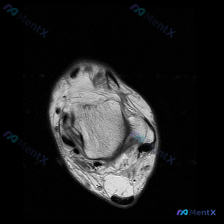

刚整理了一例踝关节MRI的软骨异常读片病例,分享给大家,整个思路还是挺典型的。 病例影像基础信息 这是一例踝关节矢状位T1序列MRI,观察目标为软骨异常,以下是所见核心信息: 影像核心所见 1. 骨骼结构: - 距骨:距骨滑车(距骨穹窿)顶部前侧可见明显骨质缺损,伴有碎骨片样结构/游离体影,骨皮质不...

看到一份踝关节MRI软骨异常的读片需求,整理一下病例信息和分析思路和大家分享: 一、病例影像基本信息 本次读片的影像为踝关节MRI-冠状位T1序列,核心问题是评估发现的软骨异常。 二、影像核心表现整理 1. 骨骼结构: 胫骨远端、距骨、腓骨远端结构完整,骨髓信号均匀,无广泛骨髓水肿或肿瘤浸润征象;踝...